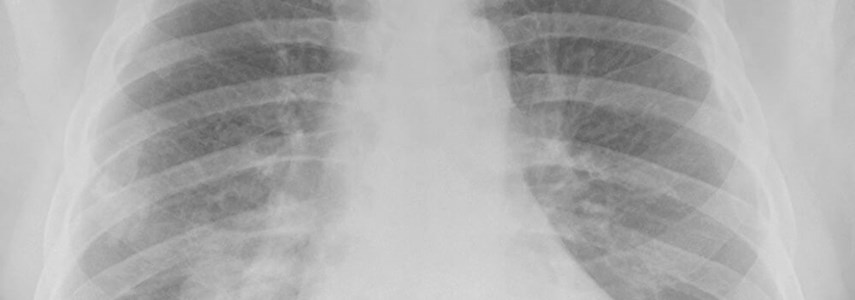

• Mesothelioma

• Asbestosis

• Pleural thickening; and

• Asbestos-related lung cancer